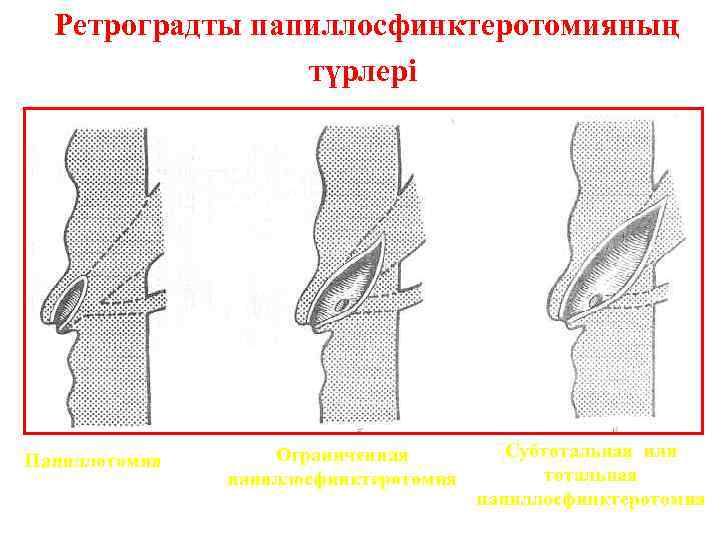

Ретроградты папиллосфинктеротомияның түрлері Папиллотомия Ограниченная папиллосфинктеротомия Субтотальная или тотальная папиллосфинктеротомия